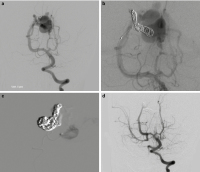

Embolisationstechniken

Abbildung 2a-d: Embolisationstechniken: Die Angiographie zeigt eine murale VGM mit prominenten Feedern aus den Aa. choroidea posteriores und einer transmesenzephalen A. perforans (2a). Nach Reduktion des arteriovenösen High-flow-Shuntvolumens durch Embolisation des Haupt-Feeders mittels Coils (2b) wurden die restlichen zwei Feeder komplett mittels Histoacryl embolisiert (2c). Die Abschluss-Angiographie (2d) zeigt eine Totalembolisation der VGM. Durch die Beendigung des Steal-Phänomens kommt es zu einer Blutflussumkehr in der rechten A. communicans posterior mit Füllung der rechten A. cerebri media über die hintere Zirkulation.

Keywords: AngiographieEmbolisationstechnikTherapieVena-Galeni-Malformation